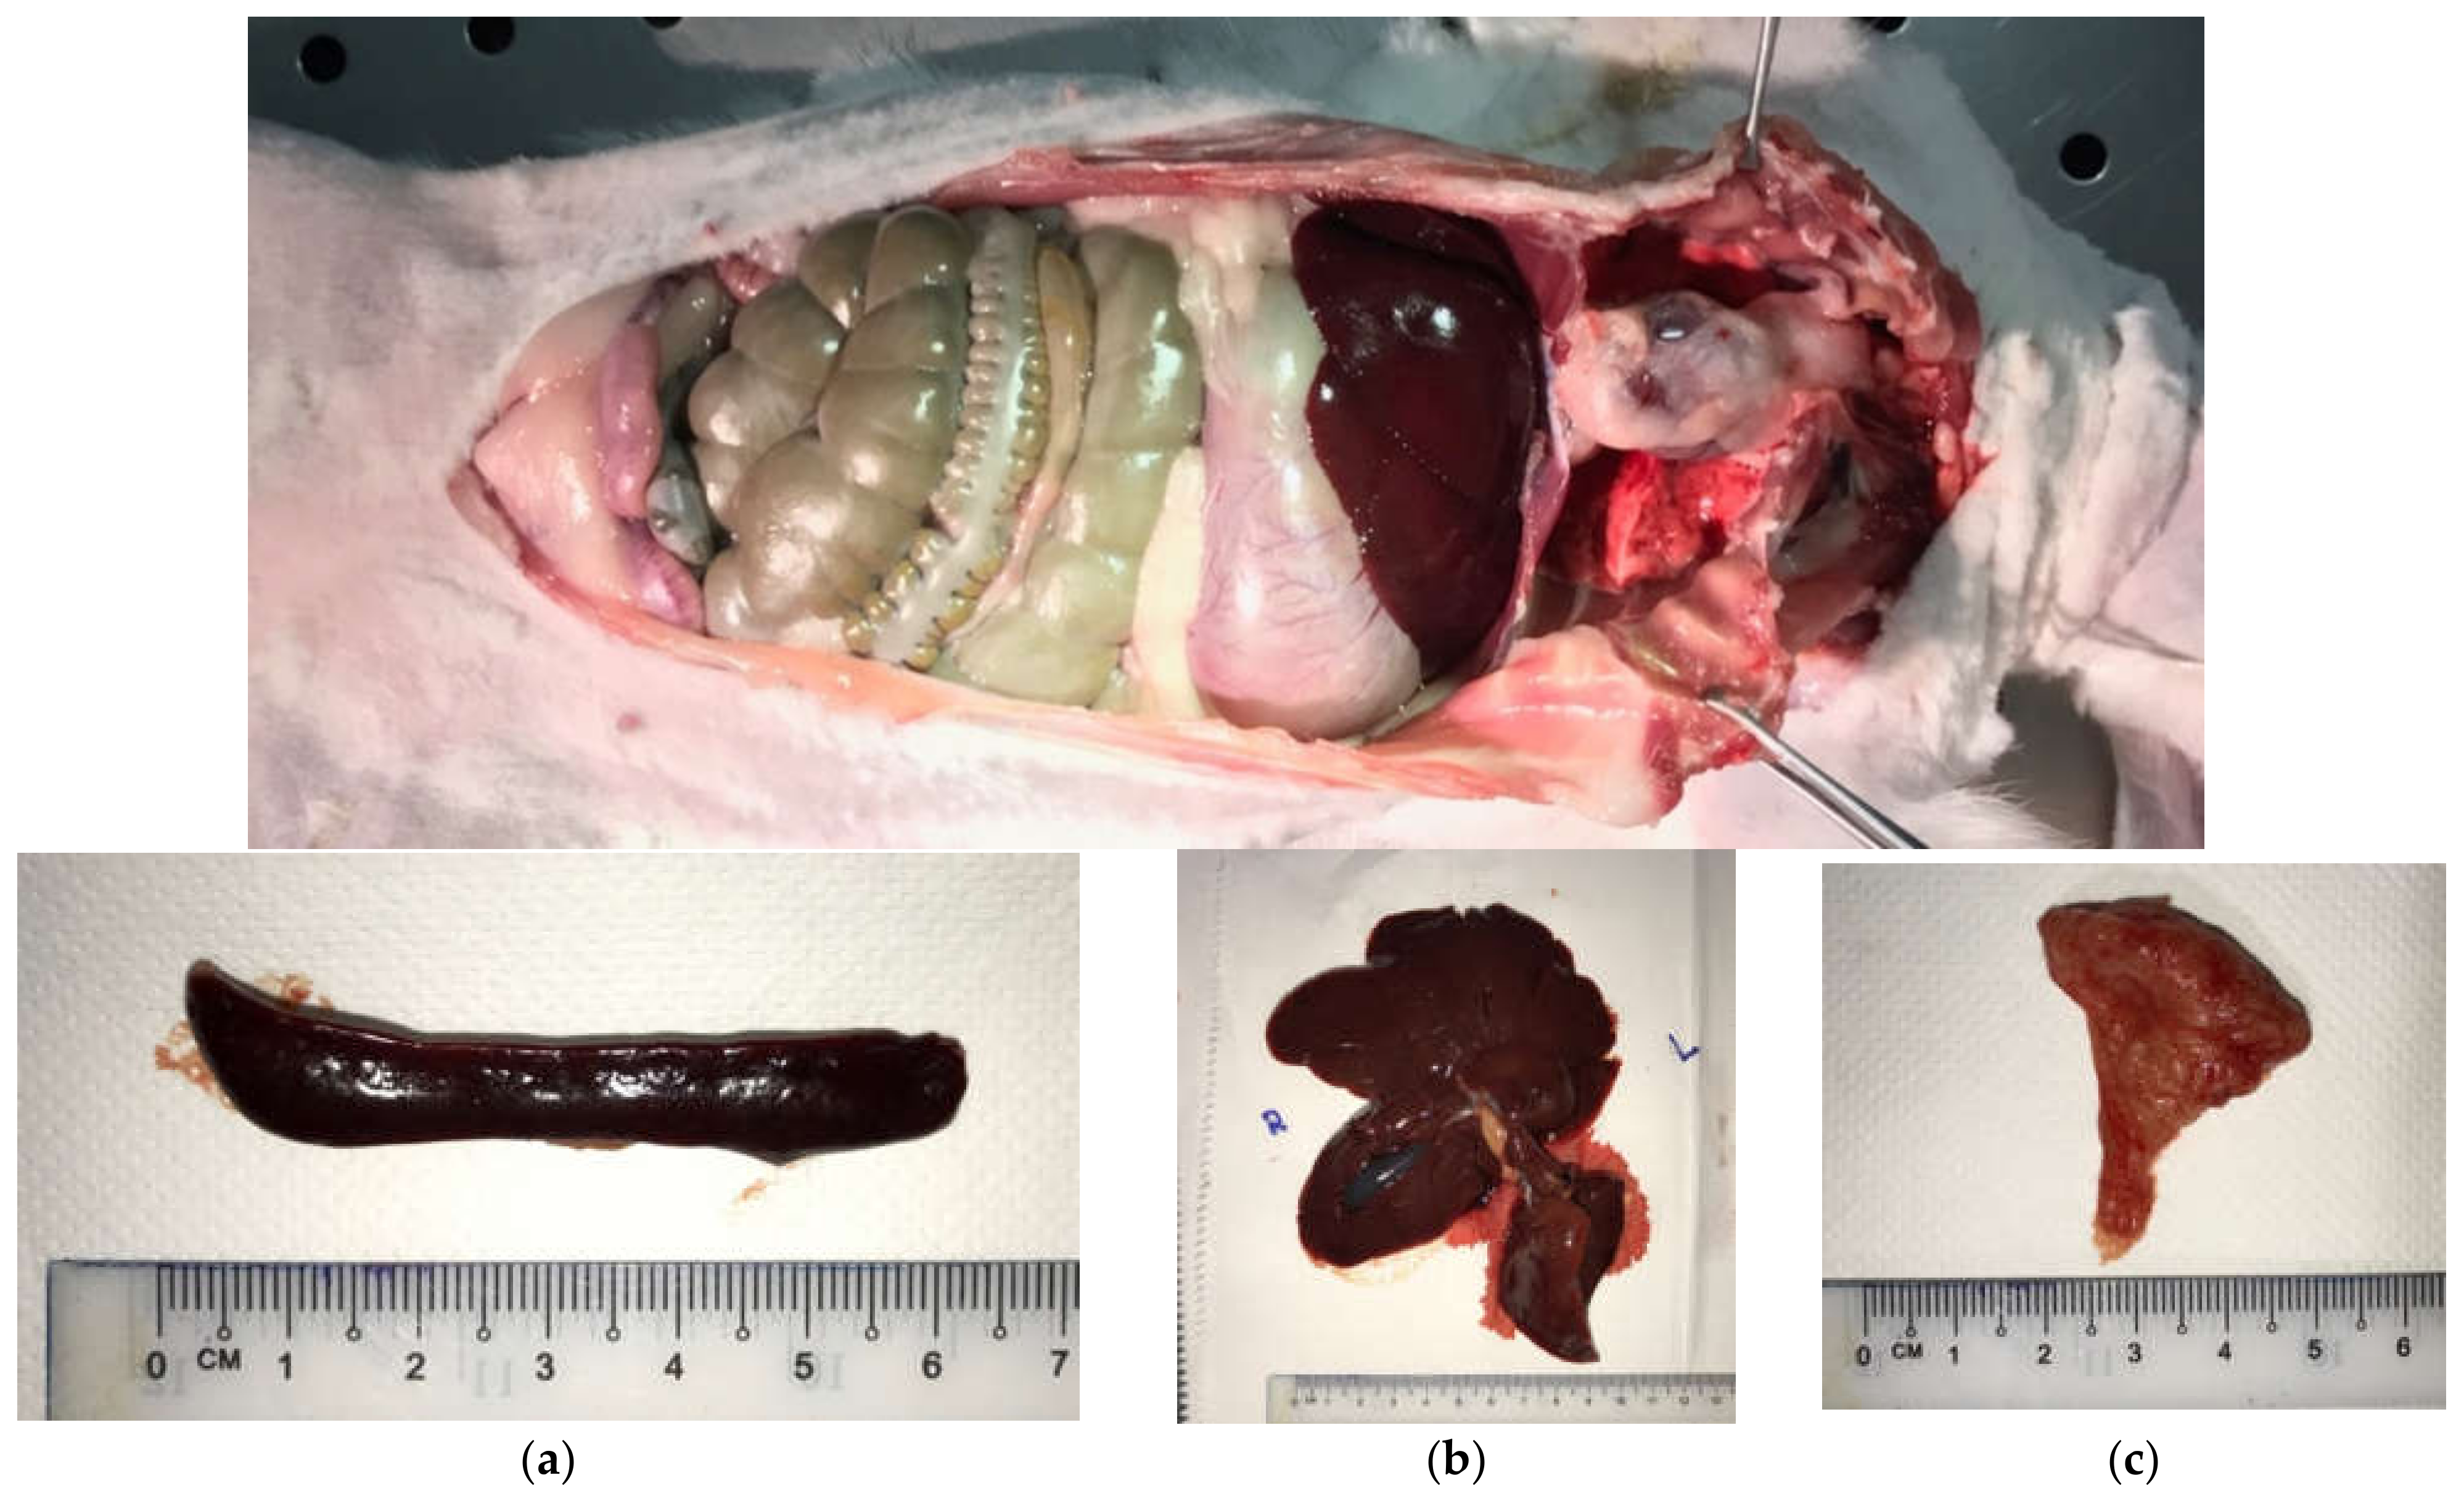

4.2.4. Sacrifice of Animals and Harvesting Lymph-Reticular Organ Tissues (for Organ-Titanium Analysis)

2.2. Analysis of Titanium Concentration in Organs

2.2.1. Liver

2.2.2. Spleen

2.2.3. Thymus